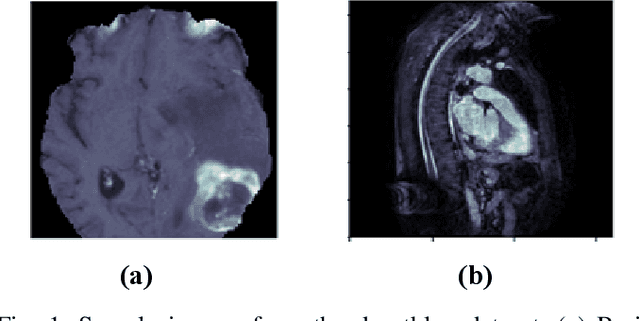

Deep learning techniques, particularly convolutional neural networks, have shown great potential in computer vision and medical imaging applications. However, deep learning models are computationally demanding as they require enormous computational power and specialized processing hardware for model training. To make these models portable and compatible for prototyping, their implementation on low-power devices is imperative. In this work, we present the implementation of Modified U-Net on Intel Movidius Neural Compute Stick 2 (NCS-2) for the segmentation of medical images. We selected U-Net because, in medical image segmentation, U-Net is a prominent model that provides improved performance for medical image segmentation even if the dataset size is small. The modified U-Net model is evaluated for performance in terms of dice score. Experiments are reported for segmentation task on three medical imaging datasets: BraTs dataset of brain MRI, heart MRI dataset, and Ziehl-Neelsen sputum smear microscopy image (ZNSDB) dataset. For the proposed model, we reduced the number of parameters from 30 million in the U-Net model to 0.49 million in the proposed architecture. Experimental results show that the modified U-Net provides comparable performance while requiring significantly lower resources and provides inference on the NCS-2. The maximum dice scores recorded are 0.96 for the BraTs dataset, 0.94 for the heart MRI dataset, and 0.74 for the ZNSDB dataset.